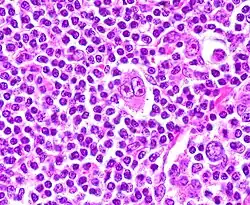

Клетки Березовского — Рид — Штернберга

Клетки Березовского — Рид — Штернберга — атипичные многоядерные гигантские клетки, пролиферация которых характерна для лимфогранулематоза[1].

- Диагностические клетки: крупные (диаметром ≥ 45 мкм), много- или одноядерные, состоят из нескольких долей, содержащих «штампованные» ядрышки размером 5-7 мкм, имеют обильную цитоплазму.

- Мононуклеарные клетки: содержат одиночное ядро с большим, похожим на включение ядрышком.

- Лакунарные клетки: содержат складчатое или многодольчатое ядро, обильную бледную цитоплазму, которая часто утрачивается в процессе приготовления срезов и ядра остаются в пустой полости (лакуне).

- Лимфогистиоцитарные клетки: имеют полиплоидные ядра, плохо различимое ядрышко, умеренно обильную цитоплазму («кукурузные» клетки).